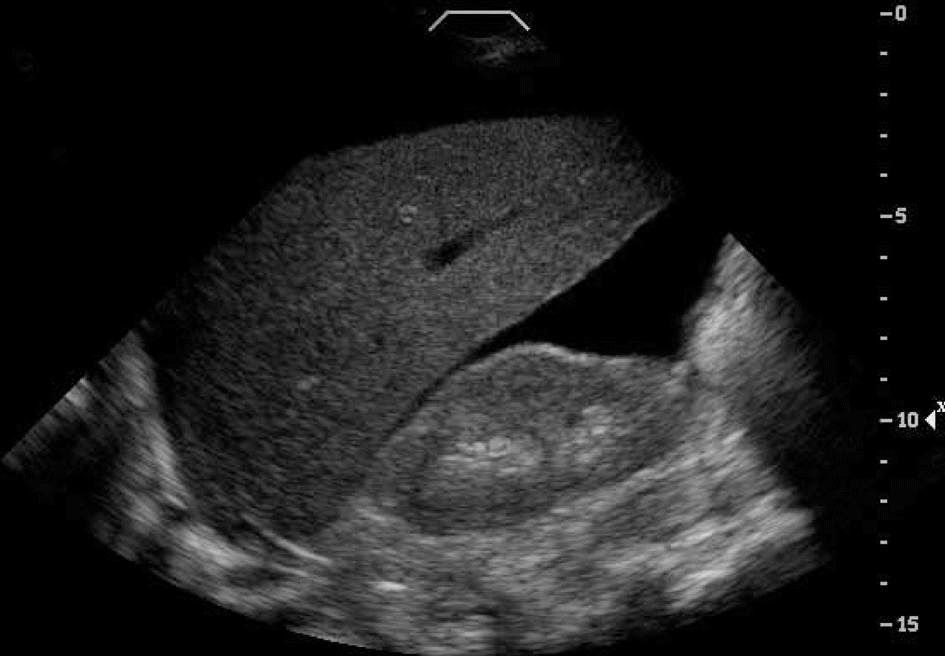

4. Do you have clinical situations in which a negative FAST exam precludes the need for a CT?

According to ATLS, a FAST is indicated only in unstable trauma patients with an unidentifiable cause of hypotension, as only hemodynamically stable patients are able to have a CT scan due to its time-consuming nature. Hence, in just such an unstable patient, a (positive) FAST does indeed preclude the need for a CT.

However, ATLS is considered out of date with respect to these mandates. Helical CTs available today are much faster than the machines of a decade ago, thus allowing some marginally stable patients to also have CT imaging performed. Similarly, the use of the FAST exam has expanded to most trauma patients, irrespective of their hemodynamic stability. Thus, today, stable or moderately stable patients may be found to have positive FASTs, yet these patients will generally get a CT before a decision is made about whether to take the patient to the OR. Still, the grossly unstable patient with a positive FAST will likely bypass the scanner en route to the OR.

Are there other scenarios when we might we safely use FAST as the sole abdominal imaging technique in evaluating a trauma patient? One group of authors state that if the patient is stable, has a negative initial FAST exam, and has no known possible risk factors for intra-abdominal injury (i.e., rib, pelvic, or spinal fracture; brief hypotension; hematuria; intoxication; persistent base deficit; head injury; distracting injury; or abdominal tenderness), then such a patient may forgo CT scanning and instead undergo serial examinations (Dunham,2008).

Of course, others disagree. A Cochrane review evaluating trauma algorithms that include ultrasound exams in patients with blunt abdominal trauma found that there is insufficient evidence from randomized controlled trials to justify promotion of ultrasound-based clinical pathways in diagnosing patients with suspected abdominal trauma (Stengel, 2005). Others have studied its use specifically in hemodynamically stable trauma patients and found it to have an unacceptably low sensitivity of 41% in this population (Natarajan, 2010).

Outside of the issue of its use in stable patients, it is important to remember that the FAST exam has limitations in identifying abdominal injuries: while good at identifying moderate hemoperitoneum, it is poor at detecting lesser amounts of blood in the peritoneum, bowel injuries, retroperitoneal bleeding, diaphragmatic tears, or bony injuries (Rhea, 2004). Hence, in a stable patient, one must have a very low suspicion for abdominal injury based on risk factors as listed above (and in question 1), to use FAST as the sole imaging technique.